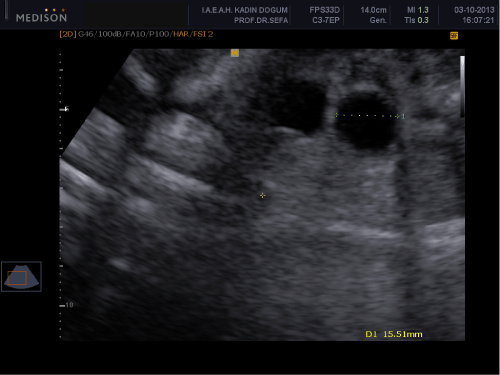

A 34-year-old woman, gravity 2, parity 0, abortion 1 is referred to our clinic at 32 weeks of gestation because of fetal intraabdominal cystic formation. She had an unremarkable prenatal course until this week. In history, she had no clinical significant coincident disease. We learned that she attended all prenatal visits regularly and she had no pathological finding in all previous visits. In the 32 weeks ultrasonography fetal biometric measurements were compatible with gestational age, amniotic fluid volume was in normal limits. Maternal blood pressure was 110/70mmHg and fetal movements were well. In ultrasonography, we detected a 15mm spheric cystic formation on the left lower side of fetal abdomen (Figure 1). The cystic formation was not related with renal structures and bladder. In Doppler sonography, we did not determine intracystic blood supply. Bilateral renal structures were evaluated normal, fetal intestines were observed normal. Because the fetus is female, cystic formation was anechoic and fetus had no accompanying genitourinary or gastrointestinal abnormalities we primarily suggested on an ovarian cyst. Due to existing fetal ovarian cyst, patient was evaluated about maternal diabetes and hypothyroidism again and resulted both in normal limits. Patient was called for a new visit two weeks later. In the 34 th week, ultrasonography fetal growth was compatible with 34 weeks gestation and amniotic fluid was in normal limits again. Only abdominal circumference was measured as 99% for this week because of fetal intraabdominal fluid. In fetal abdomen, a widespread fluid accumulation was observed (Figure 2). Ovarian cyst on the left fetal ovary was regressed and was measured 14 mm with an ellipsoid shape (Figure 3). Intestines were floating in this fluid. Fetal thorax was normal and hydrothorax was not determined. We did not observe edema in subcutaneous tissue and we evaluated as primary fetal ascites even so we performed an assessment about hydrops fetalis. Hemogram, HbA1c, VDRL, TORCH screening, Parvovirus B-19 screening, indirect coombs test and anticardiolipin IgM and IgG studies were performed. Middle cerebral artery peak systolic velcity was 55cm/sec(1,12 MOM) and was not signifying fetal anemia. We recommended fetal karyotyping to patient because it could be an onset of fetal hydrops. However, patient did not accept karyotyping. All screenings were evaluated normal. Fetal cardiac examination was normal. Patient was called for a visit two weeks later again. At the next examination in the 36th weeks of pregnancy, fetal ultrasonography was completely normal. We have not observed any fetal ovarian cyst and fluid in fetal abdomen was completely regressed. Patient had a 3400 gr healthy baby on the 40th weeks of her pregnancy. No abnormal finding determined in postnatal abdominal ultrasonography.

Figure 1: 15mm spheric cystic formation on the left fetal ovary.